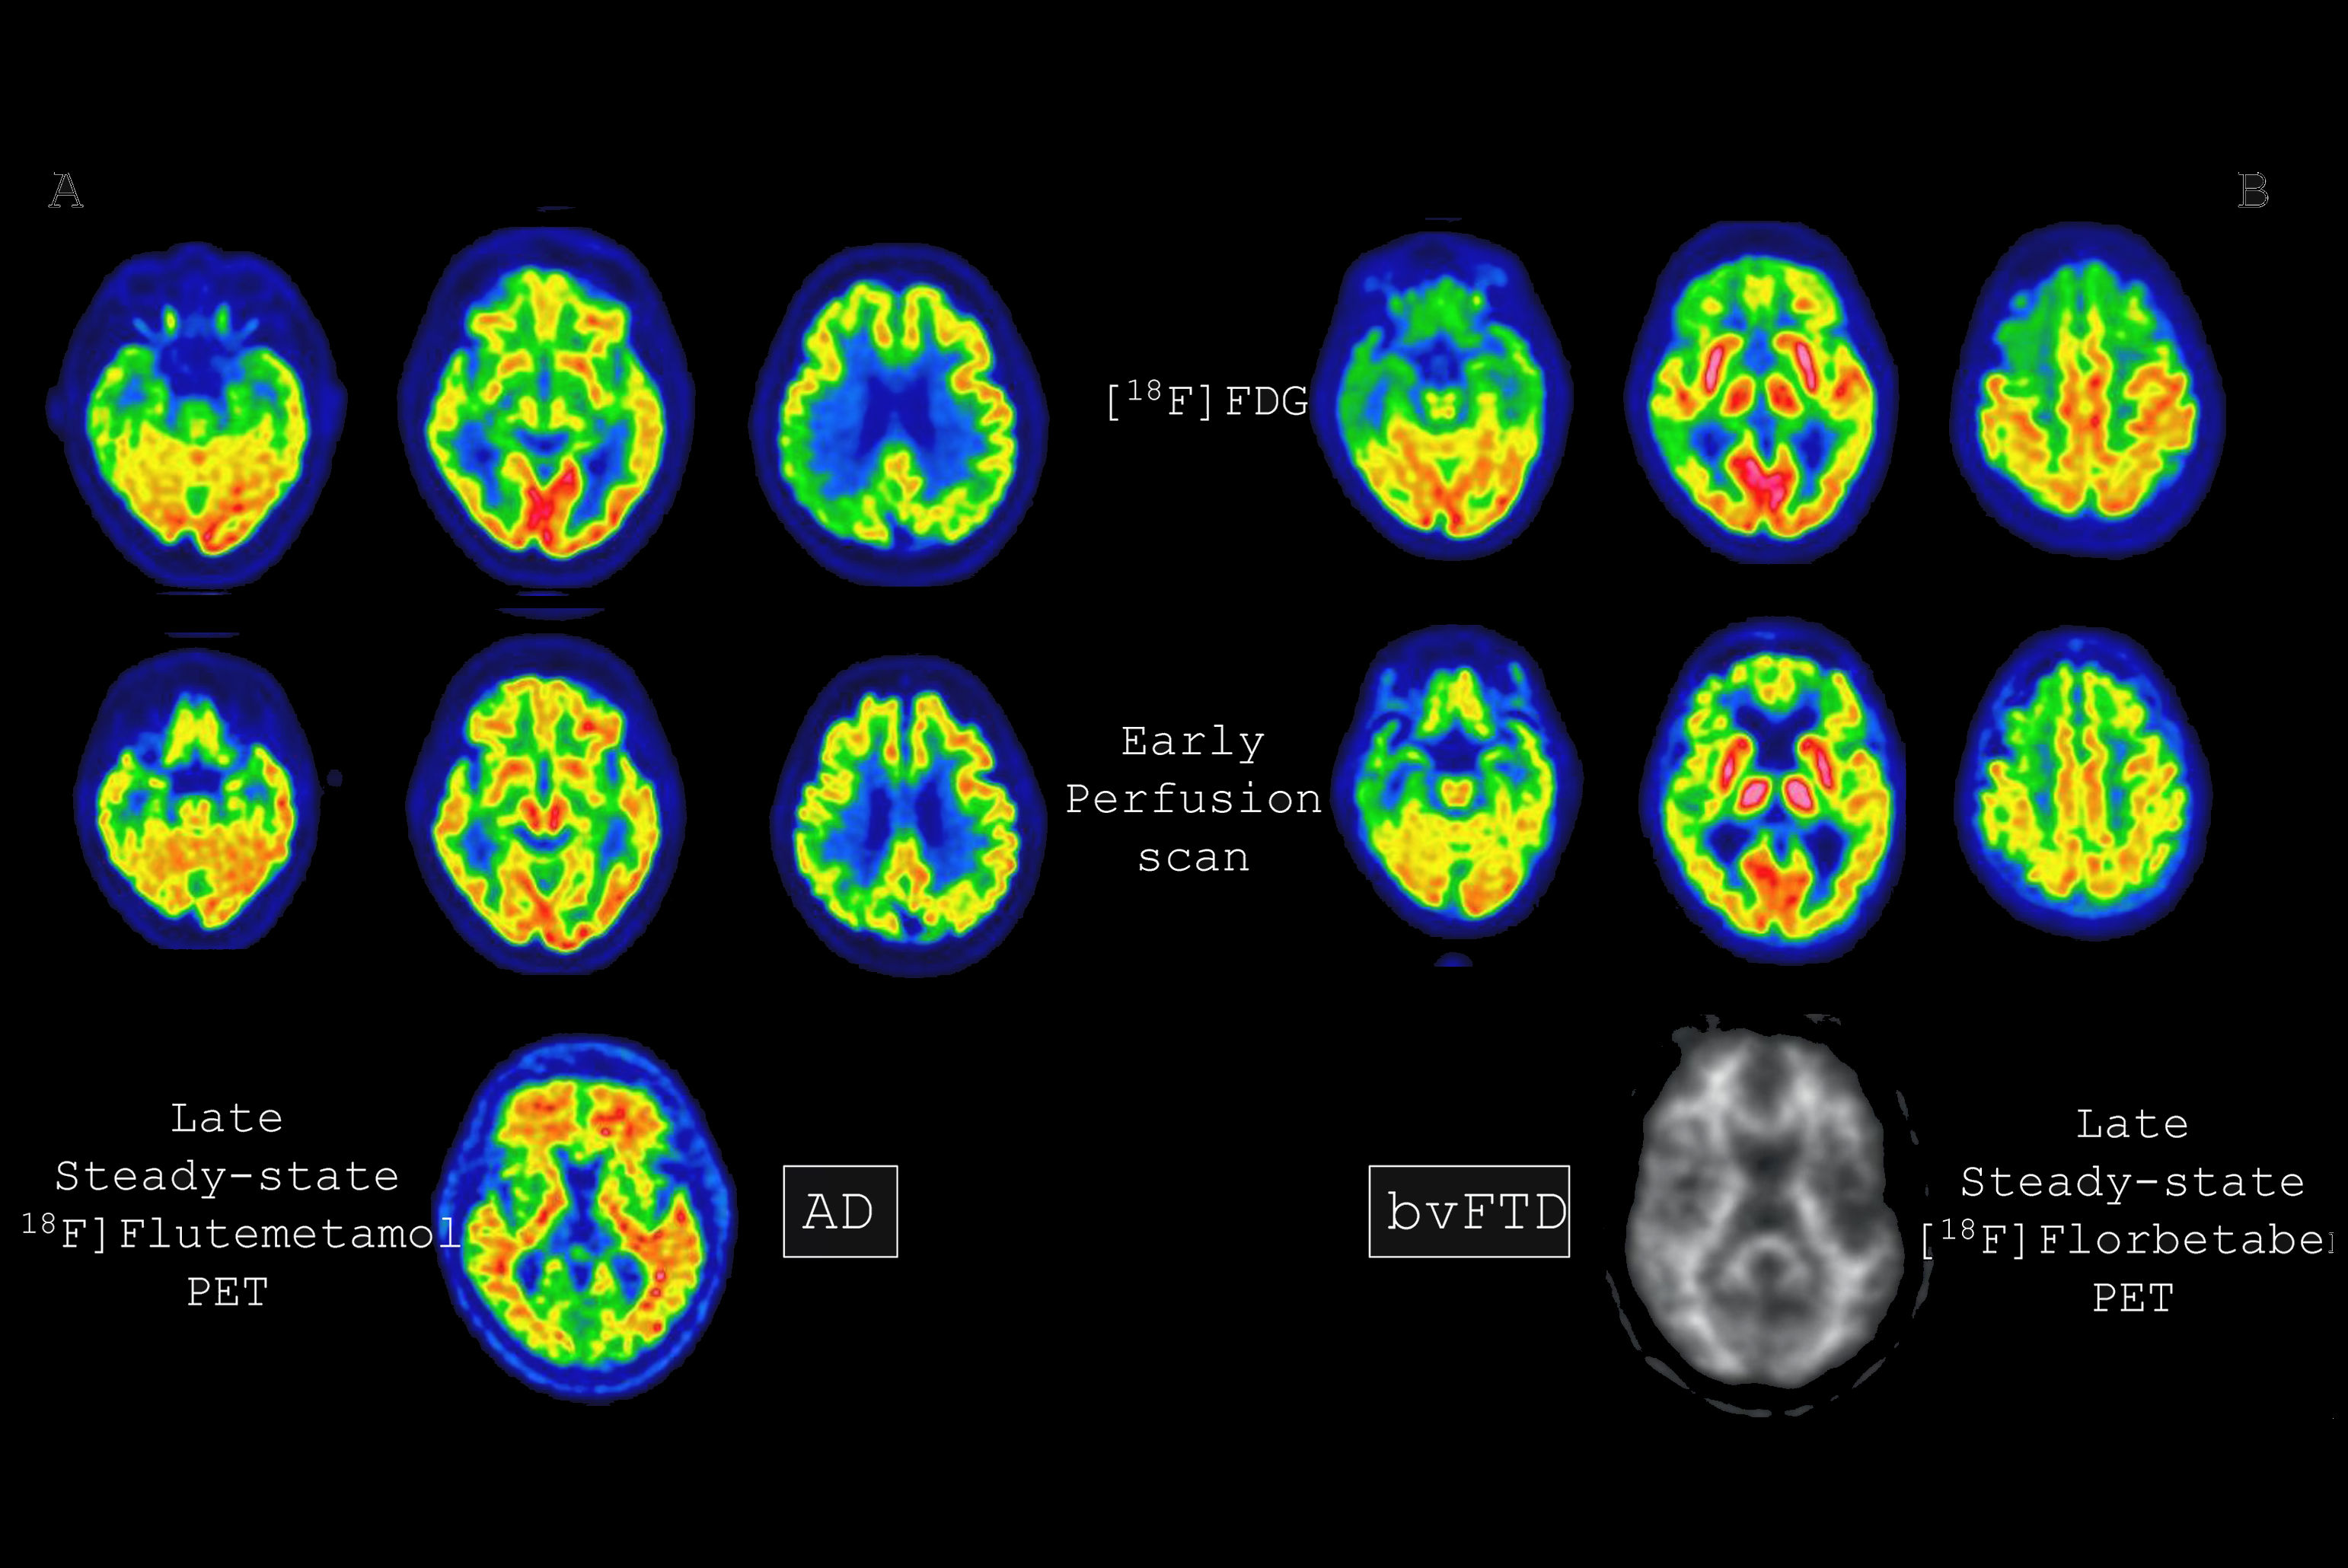

Namely, individuals receiving theranostic treatments not only receive therapeutic drugs but also radiotracer injections and undergo multiple PET scans and dosimetry imaging, which involves multi-timepoint SPECT scans. Add typical labs for oncology, and all of this adds up, Bradshaw said.

“Just as we're starting to tackle things like SUV values [standard uptake values] and trying to harmonize and standardize that from one system to another for diagnostic purposes, now we have this huge new challenge with theranostics where we now need to keep track in some way of the treatments that we're giving to patients and to try and quantify the responses to those treatments,” Siegel said.